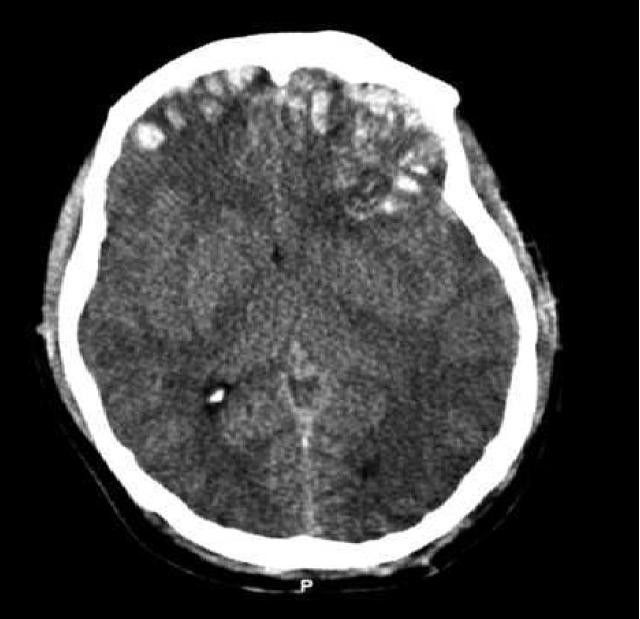

- Factores relacionados con la lesión en el trauma craneoencefálico: Si hay presencia de lesión en el tronco cerebral, el nivel de mortalidad aumenta significativamente. De igual manera, las lesiones que ocupan espacio en el cerebro tienen peor pronóstico que las lesiones difusas. Así mismo, el aumento de la presión dentro del cráneo puede generar mayores consecuencias, tanto físicas como cognitivas.